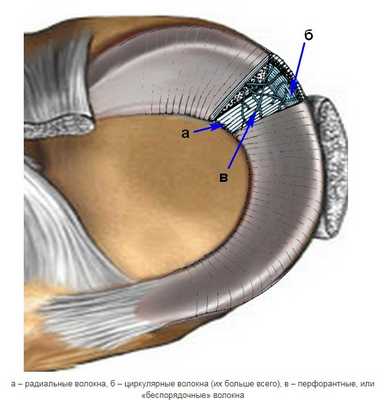

Мениск - это одна из значимых структурных частей коленного сустава, выполняющая роль стабилизатора и амортизатора колена, балансировщика нагрузки. Важнейший орган в данном отделе не в единственном своем виде: он представлен медиальным и латеральным телами. Что они представляют собой? Это волоконно-хрящевые образования на коллагеновой и эластиновой основе, отличающиеся высокой прочностью, упругостью и прекрасной эластичностью. Мениски имеют серповидную форму, а располагаются между сочленяющимися суставными поверхностями, разделяя бедренную и большеберцовую кости. Своеобразные хрящи иногда называют хрящевыми прокладками.

Несмотря на предельную физиологическую прочность, менисковые тела не застрахованы от повреждений. А особенно от патологических разрывов, которые могут произойти на почве различных травм колена. Такой неблагополучный эксцесс чаще случается в момент занятий спортом, при осевых физических нагрузках в комбинации с ротацией голени. Часто для устранения дефекта хряща применяется операция на мениске коленного сустава, послеоперационный период после которой имеет свои ограничения. Если травма несерьезная, то, в принципе, она поддается лечению и консервативно. В любом случае необходимо пройти специализированную диагностику, чтобы была назначена грамотная терапия.